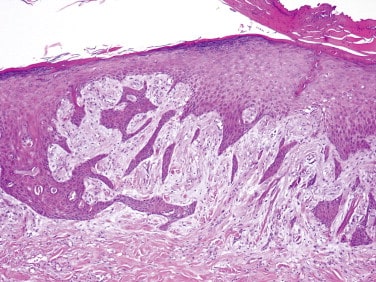

एपिडर्माइड सिस्ट को सबेसियश, केराटिन या एपिथेलियल सिस्ट भी कहा जाता है। यह छोटी और सख्त गांठ है जो त्वचा के अंदर विकसित होती है। ये बहुत आम सिस्ट है और धीरे-धीरे विकसित होती है। इस सिस्ट के कोई अन्य लक्षण नहीं होते हैं और न ही यह कैंसरस होती है। आमतौर पर यह सिस्ट चेहरे, सिर, गर्दन, पीठ और जेनिटल्स में होते हैं। इनका साइज ¼ इंच से 2 इंच तक हो सकता है। इनके अंदर पीले रंग का गाढ़ा, दुर्गंधयुक्त पदार्थ भरा होता है। आमतौर पर इसमें दर्द नहीं होता इसलिए इसे नजरअंदाज कर दिया जाता है।

एपिडर्मल सिस्ट केराटिन के जमा होने के कारण होता है। केराटिन एक प्रोटीन हैं जो त्वचा की कोशिकाओं में अपने आप बन जाता है। यह सिस्ट तब बनता है जब प्रोटीन हेयर फॉलिकल और त्वचा की किसी समस्या के कारण स्किन के नीचे फंस जाता है। यह सिस्ट अक्सर एचपीवी संक्रमण, मुंहासे या धूप के संपर्क में अधिक आने के कारण विकसित होते हैं। जिन लोगों को मुंहासे या त्वचा संबंधी अन्य समस्याएं होती है उन्हें यह सिस्ट होने की संभावना बढ़ जाती है।